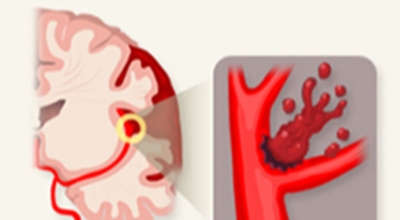

고혈압성 뇌출혈의 원인은 고혈압만이 아니라 터지기 쉬운 상태의 혈관에도 있다고 생각이 가능하지만, 아직까지 발생병리는 완전히 해명이 되지 않은 상태예요. 현재 생각 되는 것은 뇌내세 소동맥, 보통과 다르게 분기부의 혈관벽에 변화가 일어나서 연약해진 곳이 내압을 이겨내지 못하고 팽배해서 터져서 출혈을 한다는 것이죠. 뇌출혈이 일어나는 장소는 내포 부근이 가장 많다고 하며 이 부분의 중대뇌동맥의 가지가 터져서 출혈해요.

뇌출혈의 원인은 아주 다양한것으로 알려져 있답니다. 그중에서 가장 가장 저명한 뇌출혈 까닭으로는 고혈압을 꼽을 수 있습니다. 뇌출혈 발생원인이 되는 약 70%를 차지하는 고혈압은 혈관내 압력이 높은채로 쭉되게되면 세동맥혈관이 괴사되어 미세동맥류가 되는데 이는 파열되어 뇌출혈을 발생시킬 수 있죠. 그리고 외부의 쇼크으로 인한 뇌출혈도 생기게 될 수 있다고 하며, 당뇨, 뇌동맥류, 뇌종용과 같은 다양한 원인이 있답니다.